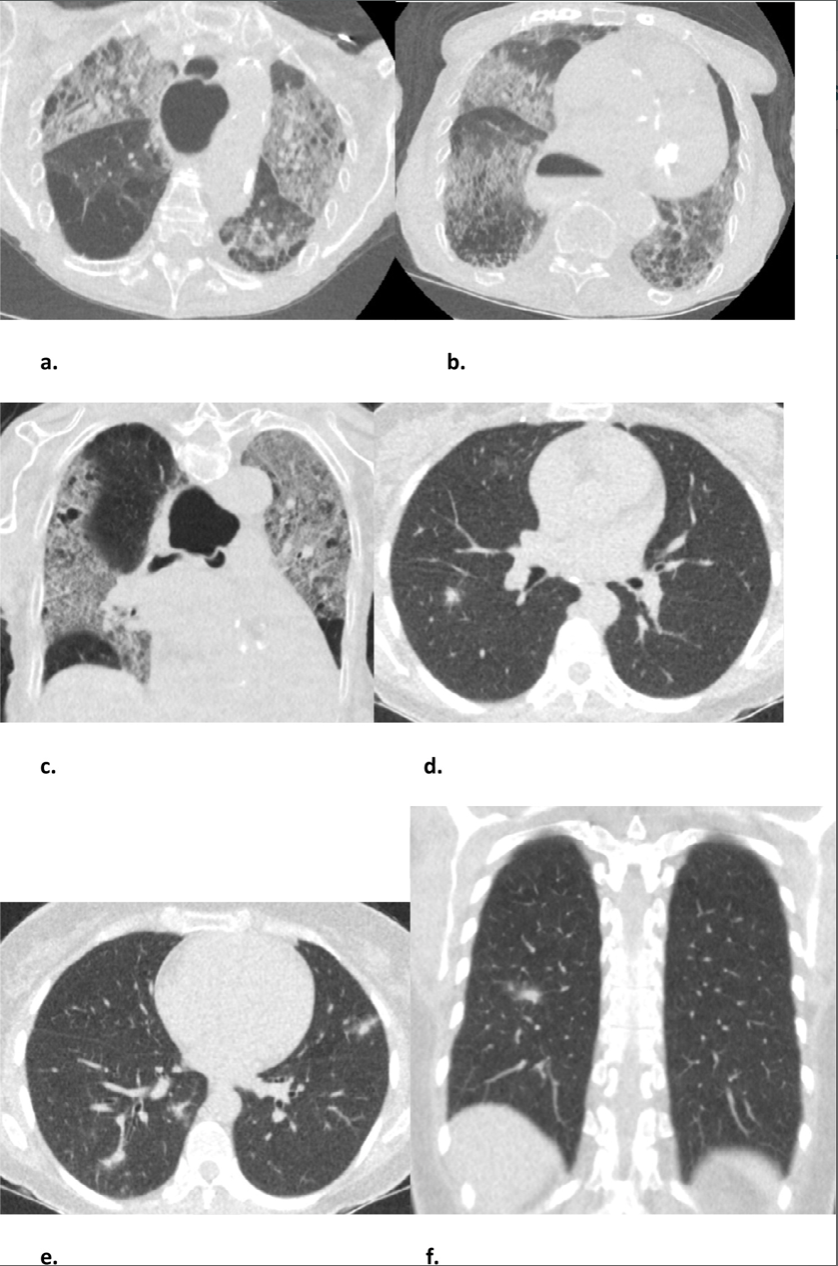

Pairing Chest Ct And Co Rads Gives Rapid Test Result For Some Covid 19 Patients